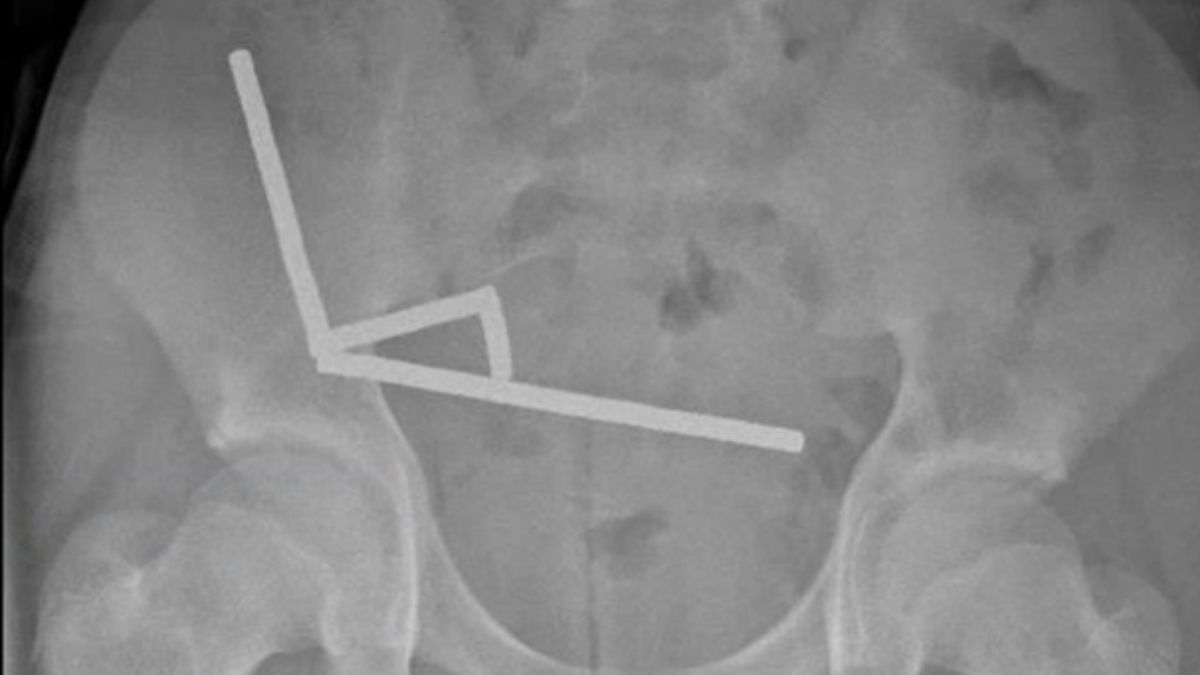

Újabb életveszélyes kihívás miatt került a műtőasztalra egy tini Új-Zélandon

Életmentő műtéten esett át egy új-zélandi tinédzser, aki veszélyes online kihívást teljesített. A tizenéves közel 200 mágnest nyelt le, azok azonban összekapcsolódtak a beleiben, és szövetelhalást okoztak.